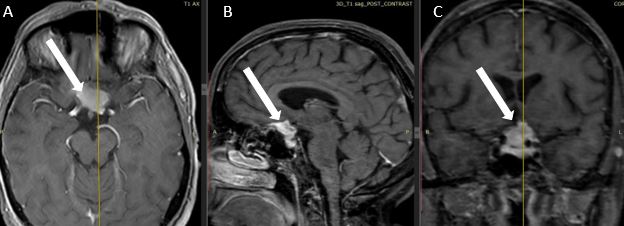

В нейрохирургическую клинику ГАУЗ «Межрегиональный клинико-диагностический центр» г. Казани обратилась женщина 63 лет с жалобами на ухудшающееся зрение. При выполнении нейровизуализации выявлена менингиома бугорка основной кости (рис. 1).

Рисунок 1. – МР-томограммы с контрастным усилением пациентки с менингиомой бугорка основной кости, белой стрелкой указана менингиома. А – аксиальная проекция, B – сагиттальная проекция, С – коронарная проекция

Fig. 1. Contrast-enhanced MRI scans of the patient with meningioma of the tuberclum sellae: a — axial view; b — sagittal view; c — coronal view; the white arrow indicates the meningioma.